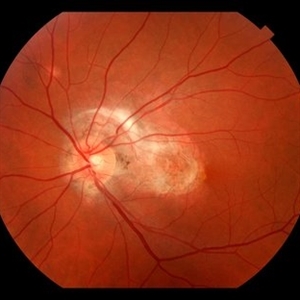

Histoplasmosis Capsulatum Retinitis OS

Histoplasmosis Capsulatum Retinitis OS

Dec 20 2021 by Brad Lovelace

Color SLO image OD of a 63-year-old woman with presumed ocular histoplasmosis syndrome OS observed for change.

Photographer: Cathy Harsma, COA

Imaging device: Optos Ultra-Widefield

Condition/keywords: histoplasmosis, presumed ocular histoplasmosis syndrome (POHS)